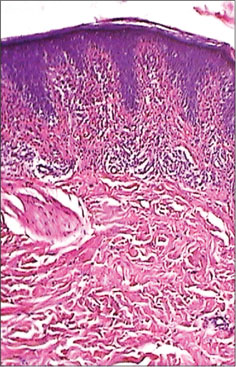

A 10-year-old boy presented with pruritic erythematous patch and plaques over lower trunk, flank, and buttocks from 5 years ago [Figure 1]. He was initially diagnosed with recalcitrant pediatrics eczema for about 5 years and was treated with topical steroids and emollient by his family physician that was with minimal improvement. Topical steroids, urea, and emollients gave temporary relief. Review of systems was otherwise negative. The patient’s past medical history has otherwise been unremarkable. On examination, he had some irregular erythematous scaly patches on the lower trunk and buttocks and a well-defined erythematous 8 cm × 6 cm patch over left flank [Figure 2], involving <10 href="https://www.thieme-connect.com/products/ejournals/html/10.4103/ijmpo.ijmpo_229_17#FI_3" xss=removed>Figure 3]; no atypical cells were seen. Lymphocytes were CD3 and CD4 positive and negative for CD8, CD20, and CD30. No T-Cell receptor gene rearrangements were found.

| Figure. 3 (a) Histopathological feature of large plaque parapsoriasis. Sporadic epidermotropism of lymphocytes, mostly in basal layer and dermis and mild interstitial infiltrate of small lymphocytes (H and E, ×100)